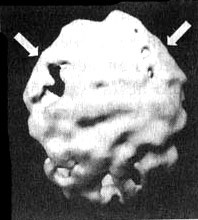

Болезнь Альцгеймера

Трехмерное изображение поверхности, вид сверху. Обратите внимание на выраженно сниженную активность в теменных долях (см. стрелки).